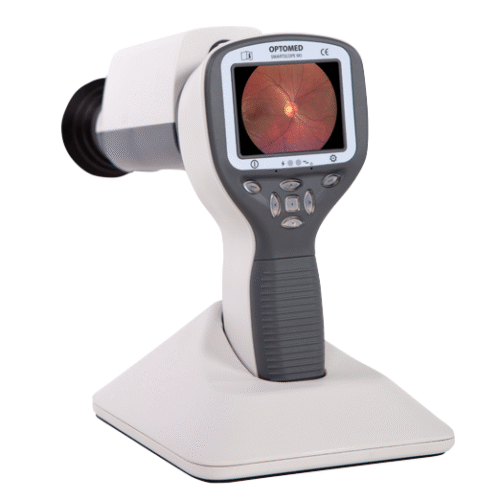

Horus Digital Diagnostic Set DSC 200P

Description

Technical Specifications